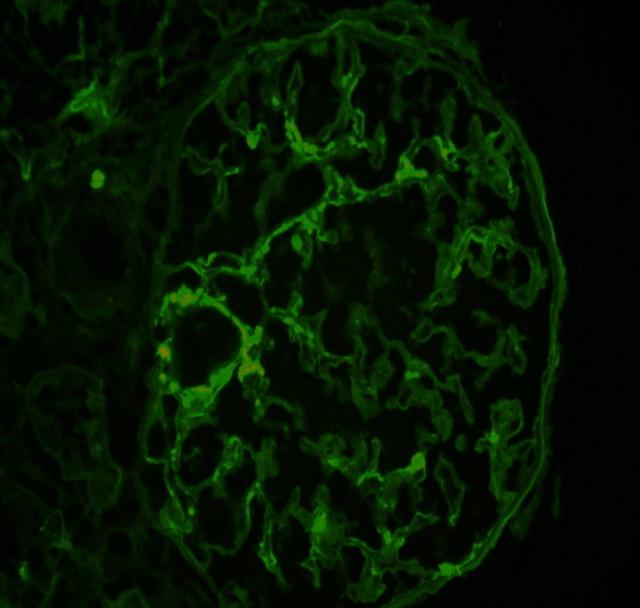

Falling through the cracks of vasculitis classification-a report of three patients.

NDT Plus. 2011 Oct;4(5):327-30. doi: 10.1093/ndtplus/sfr054. Epub 2011 Apr 14.